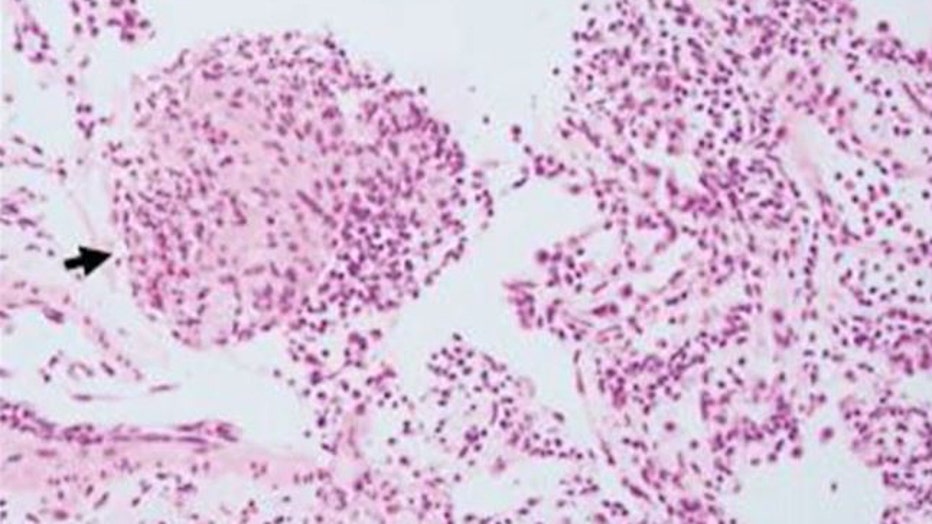

The creature was the larva of an Australian native roundworm not previously known to be a human parasite, named Ophidascaris robertsi. The worms are commonly found in carpet pythons.

The worms’ eggs are commonly shed in snake droppings which contaminate grass eaten by small mammals. The life cycle continues as other snakes eat the mammals.

The woman lives near a carpet python habitat and forages for native vegetation called warrigal greens to cook.

While she had no direct contact with snakes, scientists hypothesize that she consumed the eggs from the vegetation or her contaminated hands.